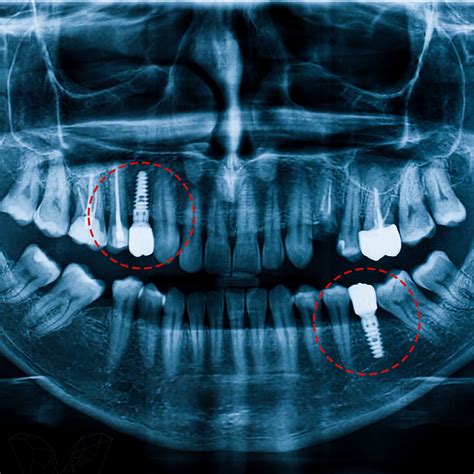

Se toma una radiografía panorámica de control al paciente verificando la posición de los implantes que corresponda a la planeación quirúrgica tomográfica.

El análisis tomográfico mostró un reborde adecuado para la colocación de implantes; se observó la silueta de los dientes de la guía diagnóstica. La función de la guía es establecer las características del tejido óseo y su relación directa con el tipo de restauración planeada, estableciendo el ángulo que guarda la cresta residual con respecto al perfil axial propuesto de la restauración final, parámetro que este tipo de recurso puede determinar y así obtener una guía tomográfica. Una vez completado el estudio, los datos se cargaron digitalmente para ser procesado con un programa de tercera dimensión.